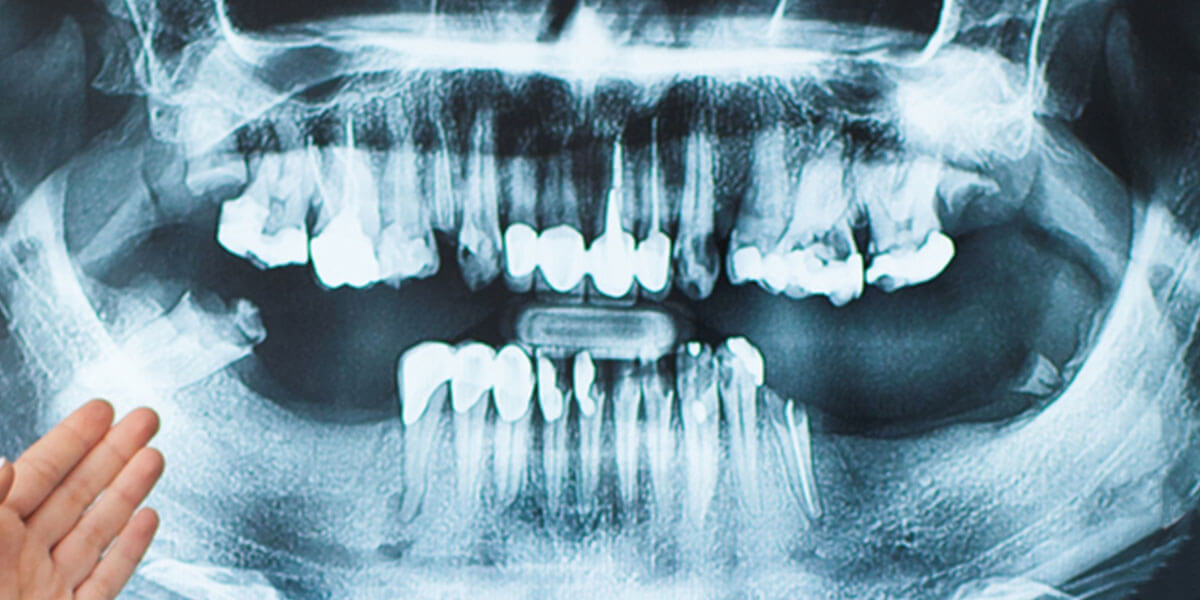

Bone Regeneration

This procedure is used to regenerate lost bone around existing teeth, or in an area where teeth have been extracted. This procedure is often performed to protect existing teeth and the tissues that keep them in place from bacterial plaque. Where bone is lost or teeth have been extracted, there may be pockets where bacteria could collect and cause damage to the existing bone and tooth structures. If there are areas of concern, the gingival tissue can be folded back to allow removal of the disease-causing bacteria and placement of membranes, bone grafts, or tissue-stimulating proteins that can encourage the body’s natural ability to regenerate bone and tissue.